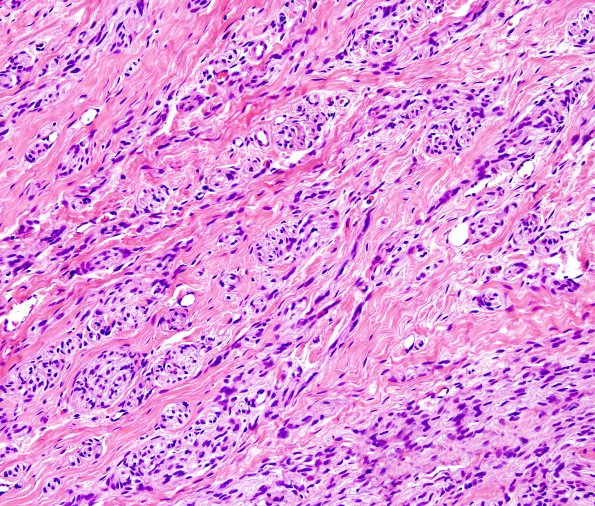

The neuroma contains mini-fascicles with interspersed collagen. (H&E)